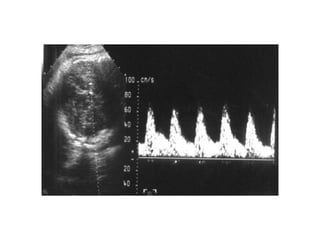

H×nh ¶nh Doppler §M rèn

Doppler §M rèn b×nh thêng

Doppler §M rèn bÖnh lý